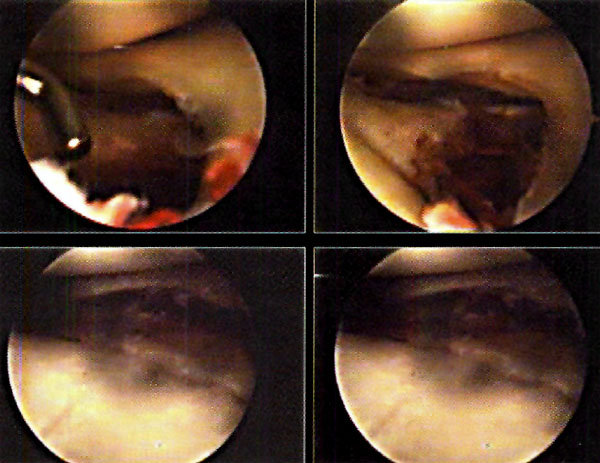

A medida que se corrige el hundimiento, controlamos mediante artroscopía si algún fragmento óseo se hipercorrige, reduciéndolo con el palpador o una cureta. (Fotos 3, 4, y 5 )

Finalizada la reducción, procedemos a rellenar el defecto óseo existente en la meseta tibial con injerto óseo obtenido de la cresta ilíaca del paciente, introduciéndolo a través de la ventana ósea efectuada en la tibia. Al mismo tiempo que impactamos el injerto controlamos bajo control artroscópico que los fragmentos de la fractura no se desplacen, o que no migre injerto óseo en la articulación. (Foto 6)

Foto 3, 4 y 5: Control artroscupico de la reducción

Foto 6: Injerto compactado